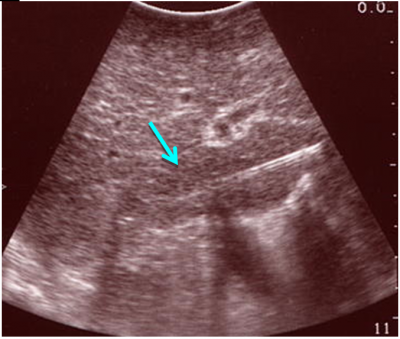

- US המראה שאת או מספר שאתות בכבד והוא כלי ראשוני לסקירה ומעקב (תצלום 29.10).

השיטות לאבחון גרורות בכבד הן: אולטראסאונד שבהכוונתו ניתן לבצע ניקור של הכבד ואבחנה של מהות הגוש. CT היא בדיקת הבחירה להדגמת גרורות בכבד ובהכוונתה ניתן לדגום את הגרורות (תצלום 37.10).

| תצלום 37.10: גרורות מרובות בכבד הנראות ב- CT (חץ). | |

|---|---|